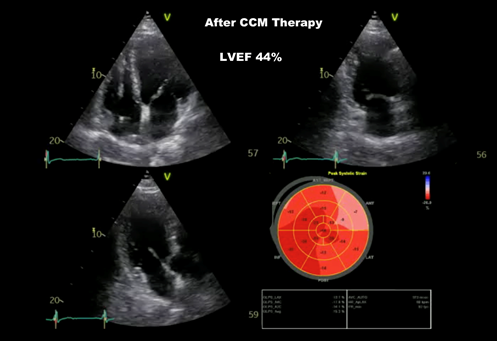

At 3months follow-up, there was a significant clinical improvement, no pedal edema, breathlessness NYHA II(previously NYHA III-IV), significant improvement in Quality of Life, and slight improvement of kidney function. The CCM Therapy was escalated to 10 hours a day. The patient could not do the 6 months follow-up, as he was out of the country for holidays with family after 8 years. At 8 months follow-up, further improvement in Quality of life, NT Pro BNP was 300 pg/ml, kidney function was normalized and echocardiographically LVEF 44%(Figure-4), mild mitral regurgitation and mild tricuspidal regurgitation, clinically no pedal edema, no pleural effusion. After a sequence of frequent hospitalization, now the patient is physically fit with CCM Therapy and GDMT.

Figure 4 echocardiography after CCM Implantation, 8 months follow up, LVEF 44%